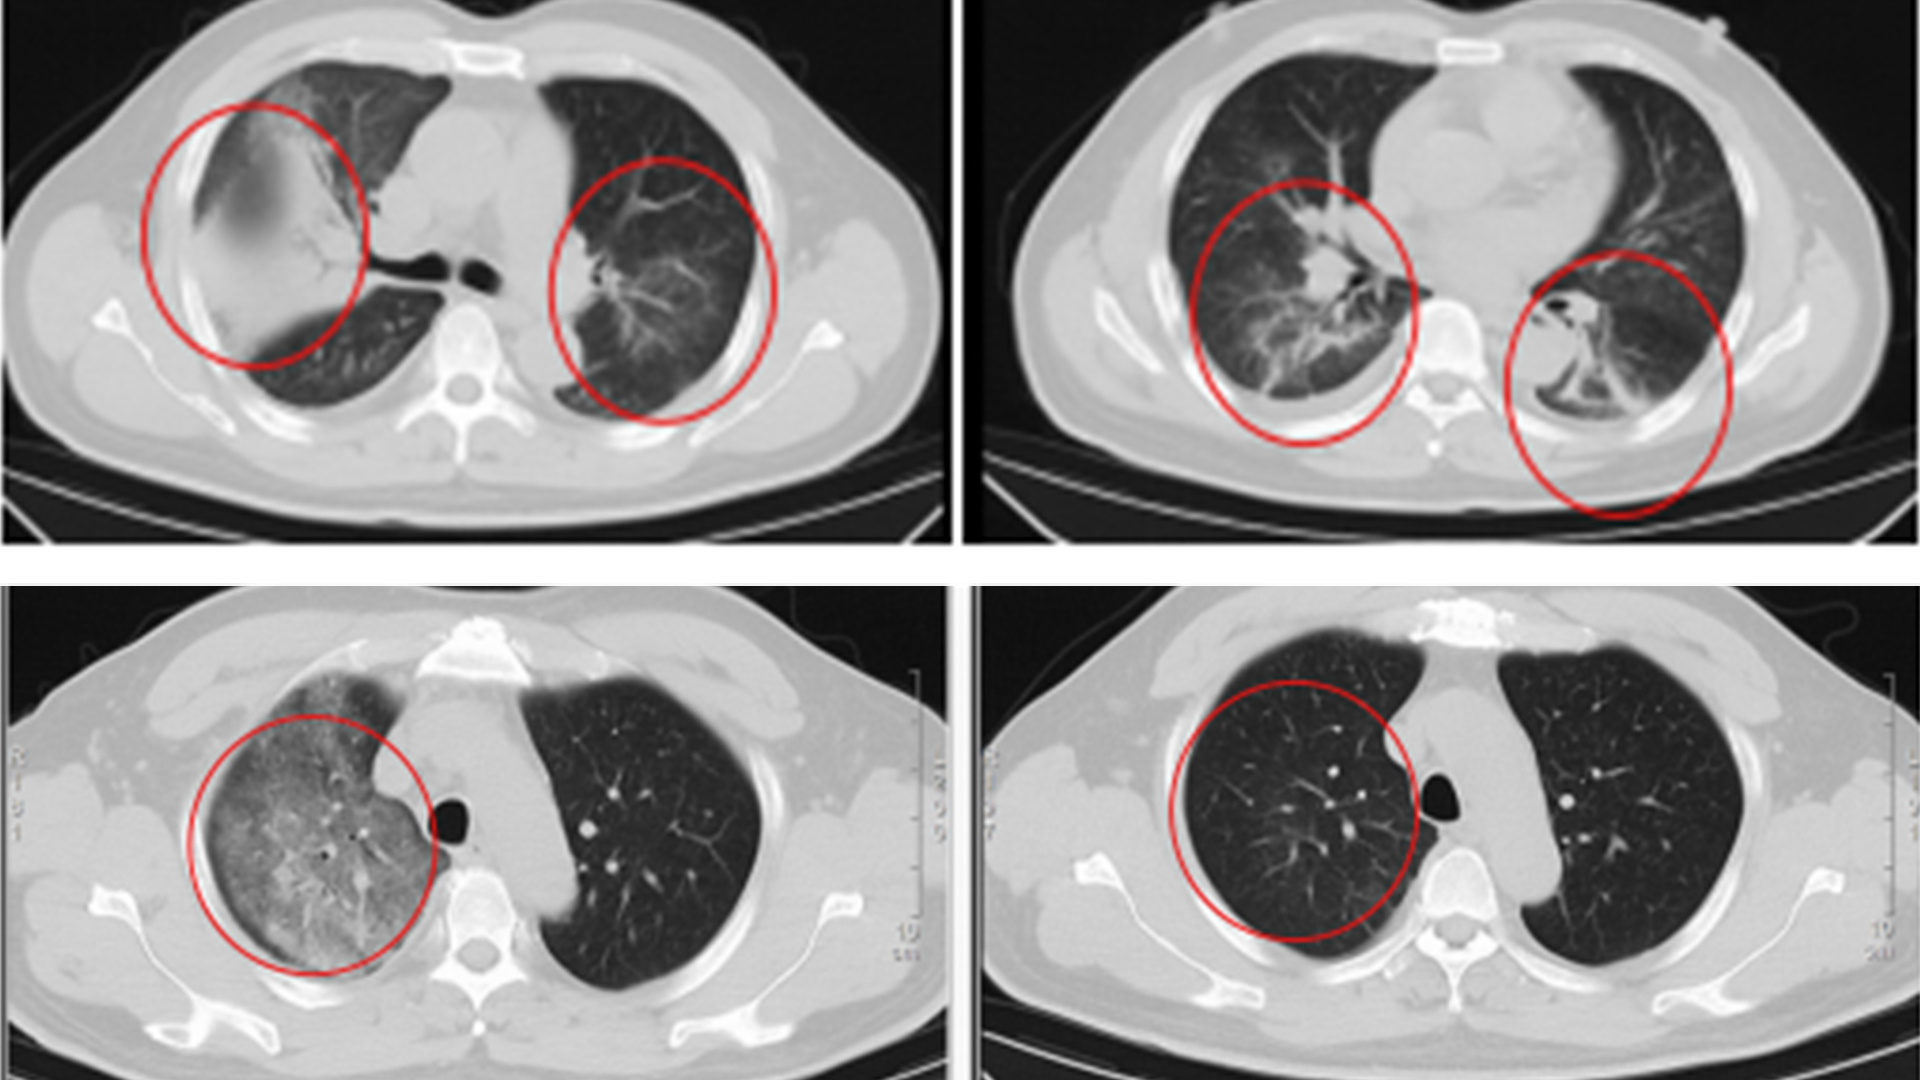

江苏确诊一例罕见传染病“Q热”,当事人病发前刚从非洲回来